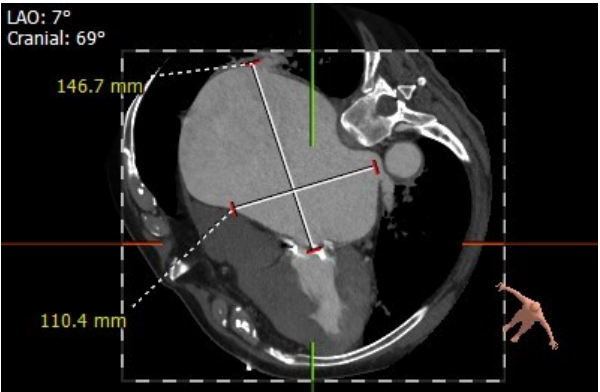

但该例患者CT分析显示,经股静脉—房间隔途径时,房间隔穿刺位置过低,难以实现输送系统自房间隔—左房—二尖瓣的通过,无法采用经股方式,在充分评估患者情况后,姜正明教授团队决定行经心尖途径入路。

面对患者复杂情况,经过充分准备,术中所有成员各司其职、配合默契,团队成员谨慎操作,心外科刘超教授团队提供充分保障、王玲云教授提供精确的超声指导,体外生命支持团队StandBy、麻醉团队、护理团队提供大力支持,瓣膜鞘管进入体内至完美释放仅用时4分钟。